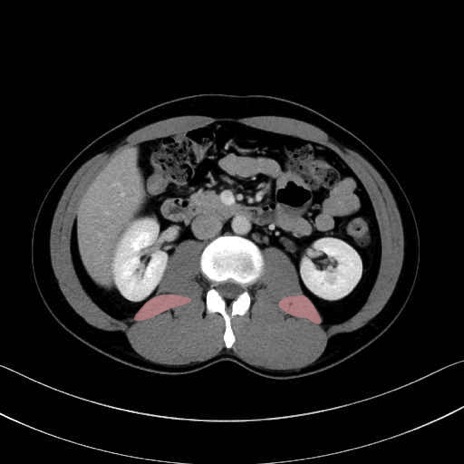

腰方形筋(quadratus lumborum muscle)のCT画像の解剖

腰方形筋 (Quadratus lumborum)

2. 腸腰筋群と骨盤底筋

大腰筋 (Psoas major)